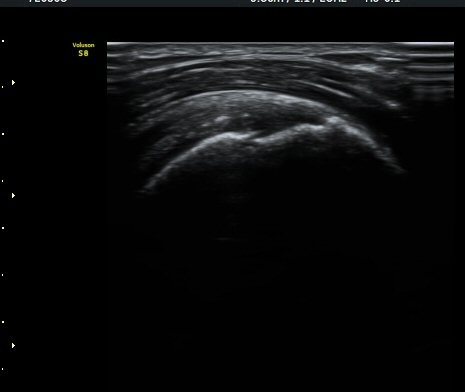

¾î±ú ¾Õ À̵ιڱ٠Ⱦ´Ü¸é°Ë»ç¿¡¼­ ÀÌºÎ¹Ú±Ù°Ç °í¶û ¾Æ·¡ ºÎÀ§¿¡¼­ À̵ιڱ٠ÀåµÎ ÁÖÀ§¿¡

¼ö¾×Àú·ù°¡ °üÂûµÈ´Ù(±×¸² 1, 2). °ß°©ÇÏ±Ù°Ç Á¾´Ü¸é°Ë»ç¿¡¼­ °ß°©ÇϱٰÇÀÇ °üÀý³»ºÎÀ§(±×¸² 3)